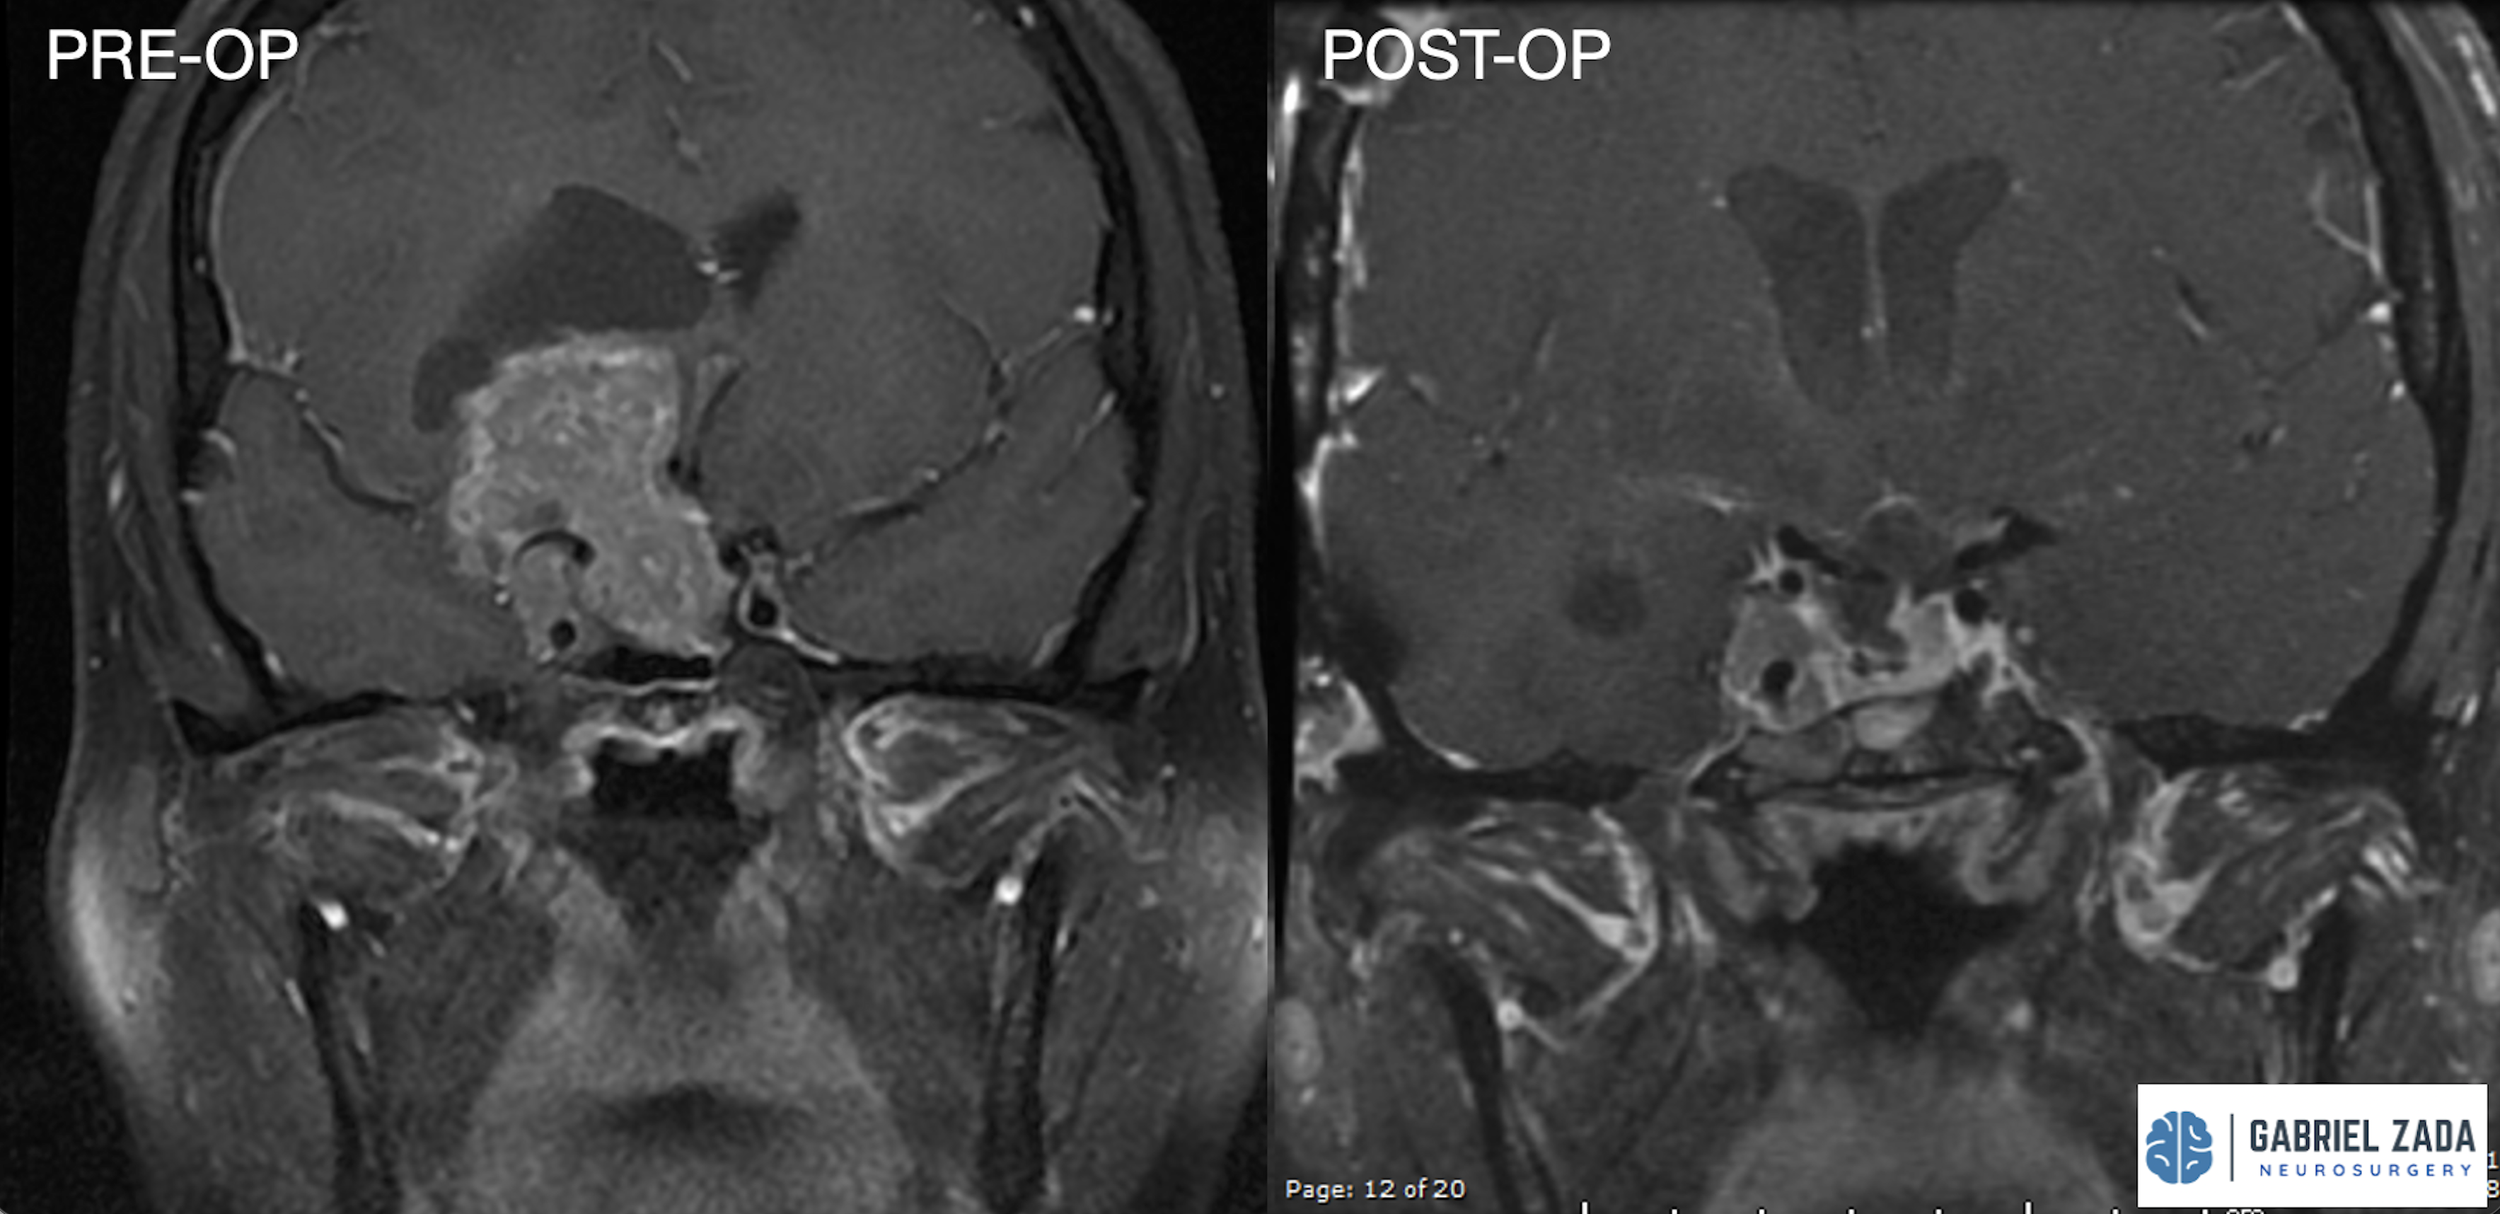

Explore this comprehensive gallery featuring pre‑ and post‑operative imaging of patients with skull‑base tumors treated by Gabriel Zada, MD, MS, FAANS, FACS. These cases highlight Dr. Zada’s expertise in advanced neurosurgical techniques and outcomes.

*Representative cases shown for educational purposes. All images de-identified. Individual results vary.